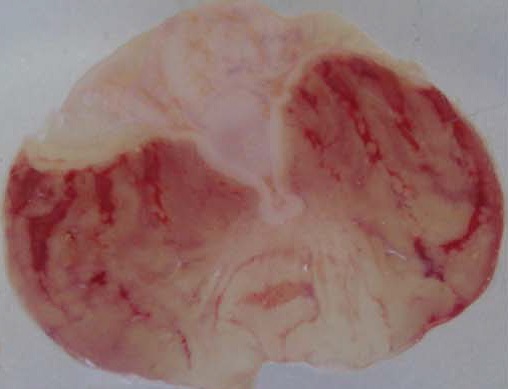

Evaluation of the healing properties of aqueous and methanol extracts of D. thollonii

Oral administration of aqueous and methanol extracts of D. thollonii at the dose of 500 mg/kg for 14 consecutive days of treatment significantly (p<0.01) decreased the area of chronic ulcer induced by acetic acid compared with the negative control group treated with distilled water. The total surface area of 29.0±2.3 mm2in the negative control was significantly (p<0.01) reduced to 18.2±0.9 and 14.5±1.6 mm2in animals which received aqueous and methanol extracts (table 3 and fig. 3). Maalox (50 mg/kg) speeded up the healing of gastric ulcer, reducing the area of the lesion to a statistically significant (p<0.01) extent by 19.2±1.8 mm2 (33.7 %) compared to the negative control group (29.0±2.3 mm2). There were no visible signs of toxicity (change in behavior or locomotory activities, or diarrhea) in animal receiving drug (extracts, Ranitidine or Maalox) for 14 days.

Fig. 3: Macroscopic study of acetic acid-induced gastric damage in rats

In fig. 3, (a): stomach of a normal control rat: no injuries to the gastric mucosa are seen and the gastric wall is normal. (b): stomach of an ulcer control rat: there is severe destruction of the surface epithelium and necrotic lesions penetrating deeply into mucosa and submucosa layers. (c): stomach of rat treated with Maalox (50 mg/kg): the gastric wall appears normally, but sometime there is edema of submucosa layer. (d): stomach of rat treated with Ranitidine (50 mg/kg): the gastric wall appears normally with all layers. (e): stomach of rat treated with 125 mg/kg of aqueous extract: there is mild disruption of the sub mucosal layer. (f): stomach of rat treated with 250 mg/kg aqueous extract: there is moderate disruption to the surface epithelium. (g): stomach of rat treated with 500 mg/kg of aqueous extract: there is mild disruption of sub mucosal layer and edema of the muscle. (h): stomach of rat treated with 125 mg/kg of methanol extract: there is mild disruption to the epithelium surface and the sub mucosal layer and edema of the serosal layer. (i): stomach of rat treated with 250 mg/kg of methanol extract: there is mild disruption to the epithelium surface. (j): stomach of rat treated with 500 mg/kg of methanol extract: there is moderate disruption of the epithelium surface although the gastric wall appears normally.